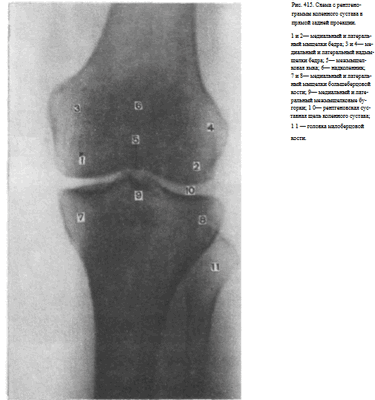

Информативность снимка. На снимке коленного сустава в прямой задней проекции определяются дистальный метаэпифиз бедренной кости, медиальный и латеральный мыщелки бедра, между которыми располагается межмыщелковая ямка. Выше мыщелков определяются медиаль-ный и латеральный надмыщелки. На фоне дистального метаэпифиза бедренной кости виден надколенник. Проксимальный эпифиз большеберцовой кости представлен медиальным и латеральным мыщелками, между

которыми определяются медиальный и латеральный межмыщелковые бугорки. На латеральный отдел метаэпифиза большеберцовой кости частично накладывается головка малоберцовой кости. Между мыщелками бедренной и большеберцовой костей выявляется рентгеновская суставная щель коленного сустава в виде неравномерно изогнутой полосы просветления (рис. 415).

Информативность снимков коленного сустава как в задней прямой, так и в передней прямой проекциях одинаковая. В передней прямой проекции несколько лучше видна структура надколенника. Информативность одномоментных снимков коленных суставов в прямой задней проекции ниже, так как каждый из суставов при этом подвергается проекционным искажениям.